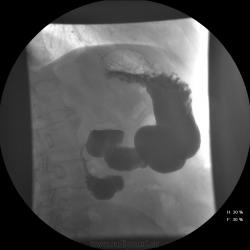

Возможно это полипы?

[[wysiwyg_imageupload:524:]][[wysiwyg_imageupload:525:]][[wysiwyg_imageupload:526:]]

А может быть то не полипы, может слизистая из желудка пролабировалась в луковичку, может это ....

А, может и пролапс есть?

[[wysiwyg_imageupload:530:]][[wysiwyg_imageupload:531:]][[wysiwyg_imageupload:532:]][[wysiwyg_imageupload:533:]]

Ответов конечно много,но: - кольцевидной панкреас у пациента нет (ни раз проводили кт - там хрон панкреатит,кисты, подозрение на образование , но это уже в течении 2 лет...) - рака ДПК, полипов, язвы нет - несколько раз проводилось ФГДС; - пролапс может и есть , но не в нем проблемы...;

... в заключениях УЗИ и ФГДС фигурирует луковица ДПК, при Rg-логическом исследовании - нисходящая часть ДПК.